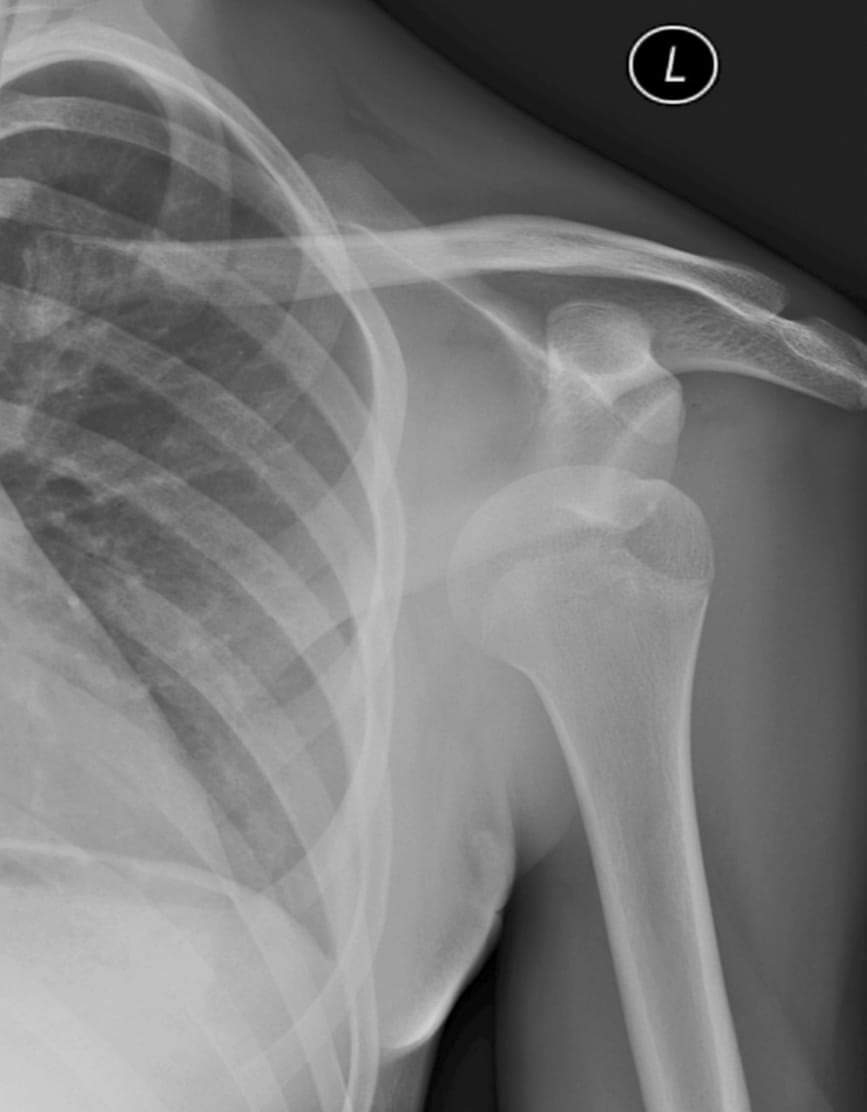

Un homme âgé de 34 ans consulte en urgence à la suite d’une douleur atroce survenue après une chute sur son épaule gauche.

Quel diagnostic évoquez-vous ?

Il s’agit d’une luxation antérieure gléno-humérale sous-coracoïdienne. Voir explications ci-dessous.

Il n’y a pas de trait de fracture de l’extrémité supérieure de l’humérus dans la radiographie de l’épaule ci-dessus.

Il n’y a pas de trait de fracture de la clavicule dans la radiographie de l’épaule ci-dessus. Cependant, il faut savoir que c’est l’os le plus fréquemment touché par mécanisme direct (chute sur le moignon de l'épaule).

L’articulation de l’épaule est la structure ostéoarticulaire la plus mobile du corps, mais aussi la plus fréquemment luxée (plus de 50 % des cas). La luxation de l’épaule est la perte de contact total et permanent entre la surface articulaire de la glène de l’omoplate et la tête humérale. La luxation antéro-interne sous-coracoïdienne est de loin la plus fréquente. C’est une urgence traumatologique diagnostique et thérapeutique, car un retard de la réduction (au-delà de 6 h) augmente le risque de compression de structures nobles vasculaires tel l’artère axillaire par dissection ou compression, ou bien nerveuses comme celle du nerf axillaire. Elle peut aboutir à long terme à une fragilité de l’articulation par déformation articulaire, instabilité ou arthrose. À retenir :